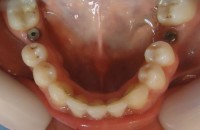

27-Finalizacion de coronas en piezas 3.6 y 4.6 27-Finalizacion de coronas en piezas 3.6 y 4.6 Deja un comentarioYou must be logged in to post a comment.